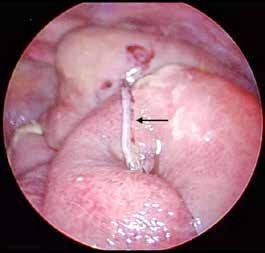

Figura 1. Lesión eritematosa-equimótica en hipogastrio producida por manillar de bicicleta (cabeza de flecha).

Figura 2. Ecografía con burbujas aéreas extraluminales en la superficie hepática sugestivas de neumoperitoneo (A, flechas). RxTA con neumoperitoneo subdiafragmático bilateral (B, flechas).